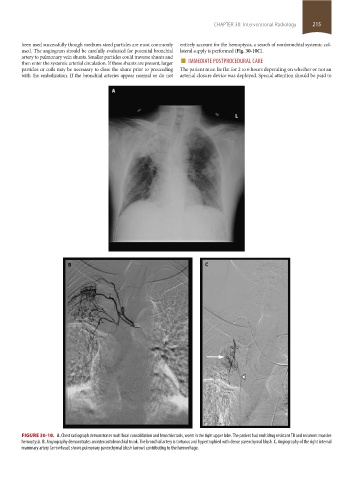

FIGURE 30-10. A. Chest radiograph demonstrates multifocal consolidation and bronchiectasis, worst in the right upper lobe. The patient had multidrug resistant TB and recurrent massive

hemoptysis. B. Angiography demonstrates an intercostobronchial trunk. The bronchial artery is tortuous and hypertrophied with dense parenchymal blush. C. Angiography of the right internal

mammary artery (arrowhead) shows pulmonary parenchymal blush (arrow) contributing to the hemorrhage.